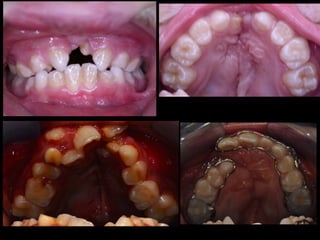

Dental anomalies in Cleft lip and palate patients

• The incidence of dental anomalies is

54%(15% normal population)

• Missing teeth

• Supernumerary

• Enamel hypoplasia

• Morphology anomalies

• Impacted teeth (1

• Missing upper lateral incisor (30-50%)

⬥In deciduous dentition some teeth could be smaller in

the cleft side

⬥Males- laterale incisor and second molar

⬥Females - central and lateral incisors

!

⬥In permanent dentition always lateral incisor

congenitally missing